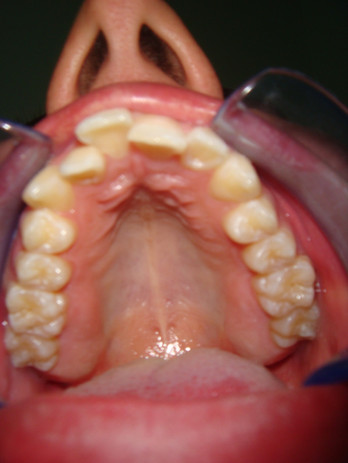

Grazie al microscopio, infatti, si riesce in modo ottimale a ristabilire l'anatomia degli elementi dentali.